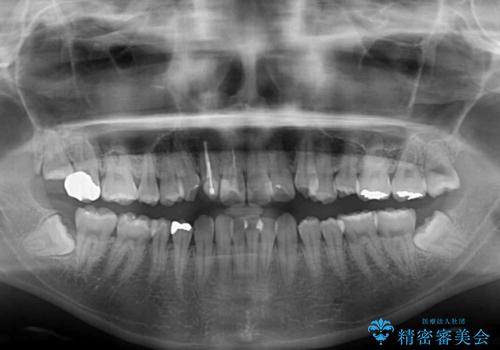

狭い上顎骨を拡大 インビザラインによる非抜歯矯正

- 上下のデコボコと奥歯の咬みにくさを気にして来院された患者様です。

上顎骨の幅が下顎骨よりも小さいので、拡大装置により骨幅を広げて上下関係を改善し、その後インビザラインにて歯並びを整えることとしました。

上下の骨幅を改善したことで、スムーズに歯列矯正を行うことができました。

奥歯の咬み合わせを改善する必要があったため、治療は長期化しましたが、きっちりと仕上げることができました。